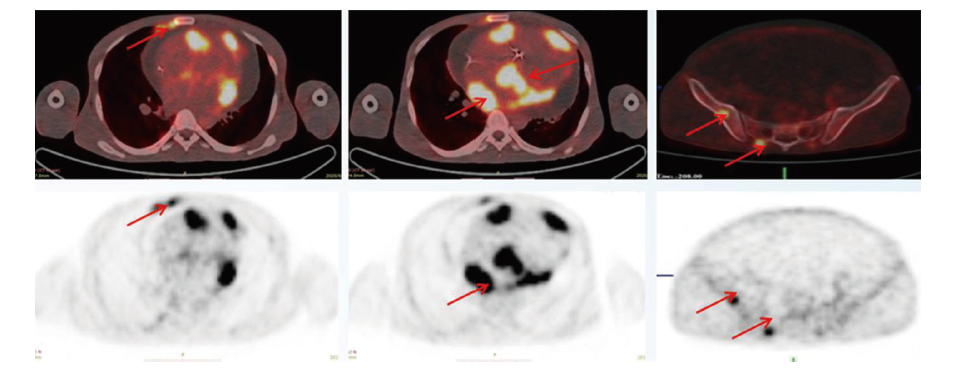

入院后治疗:结合PET/CT、病理、骨穿结果, 诊断为伯基特淋巴瘤, Ⅳ B期, 国际预后指数(international prognostic index, IPI)4分。于2020-09-07开始予甲强龙40 mg qd减瘤治疗。于2020-09-11予CDOP(cyclophosphamide, pegylated liposomal doxorubicin, vincristine, prednisone, 环磷酰胺、盐酸多柔比星脂质体、长春新碱、泼尼松)(50%)化疗。后续于2020-09-27、2020-10-23、2020-11-18分别予CD20单抗(利妥昔单抗)联合CODOXM-A(cyclophosphamide, vincristine, epirubicin, methotrexate, 环磷酰胺, 长春新碱, 盐酸多柔比星脂质体, 甲氨蝶呤)、CODOXM-B(ifosfamide, etoposide, cytarabine, 异环磷酰胺, 依托泊苷, 阿糖胞苷)、CODOXM-A方案治疗。因浆膜腔积液为使用大剂量甲氨喋呤禁忌症之一, 患者持续存在大量腹水, A方案中以替莫唑胺替代甲氨喋呤。根据方案每疗程行腰椎穿刺+鞘内注射预防中枢侵犯。2周期化疗后复查PET/CT(2020-11-18)示:心脏及纵隔大血管周围病变明显缩小, 糖代谢减低(SUVmax 2.0); 双侧胸膜病变及右肺门淋巴结代谢较前减低(SUVmax 1.5), 多处骨代谢增高灶未见显示; 心包积液, 心脏增大, 双心房明显; 右侧胸腔积液; 大量腹腔积液, 下腔静脉入口管腔扩张。靶病灶达完全缓解, 但患者持续存在大量腹水。心脏及纵隔大血管病变见图2。

旁述:根据美国国立综合肿瘤网络(National Comprehensive Cancer Network, NCCN)指南, 高危伯基特淋巴瘤首选CODOXM-A/IVAC(cyclophosphamide, doxorubicin, vincristine, methotrexate/ifosfamide, etoposide, high dose cytarabine, 环磷酰胺、阿霉素、长春新碱、甲氨蝶呤/异环磷酰胺、依托泊苷、高剂量阿糖胞苷)联合CD20单抗交替治疗4程, 年轻患者经化疗后预后好, 客观缓解率(objective response rate, ORR)达93%, 完全缓解率(complete response rate, CRR)达91%, 3年总生存率达76%[8]。该患者2周期治疗后PET/CT提示心脏及纵隔大血管周围病变明显缩小(图2), SUVmax 2.0, Deauville评分3, 虽然仍有大量腹水, 但多次腹水病理细胞学并未见肿瘤, 腹水与肿瘤无关。按照2014 Lugano评价标准[9], 疗效评价CR, 且外周血ctDNA检测阴性。